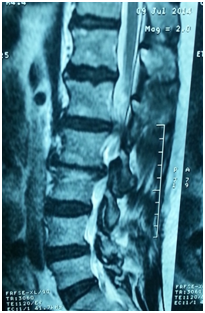

- Anterior column reconstruction with cages especially at Lumbo- sacral junction is necessary and always required to restore sagittal balance (Figure 3).

Figure 3 Flat back syndrome.